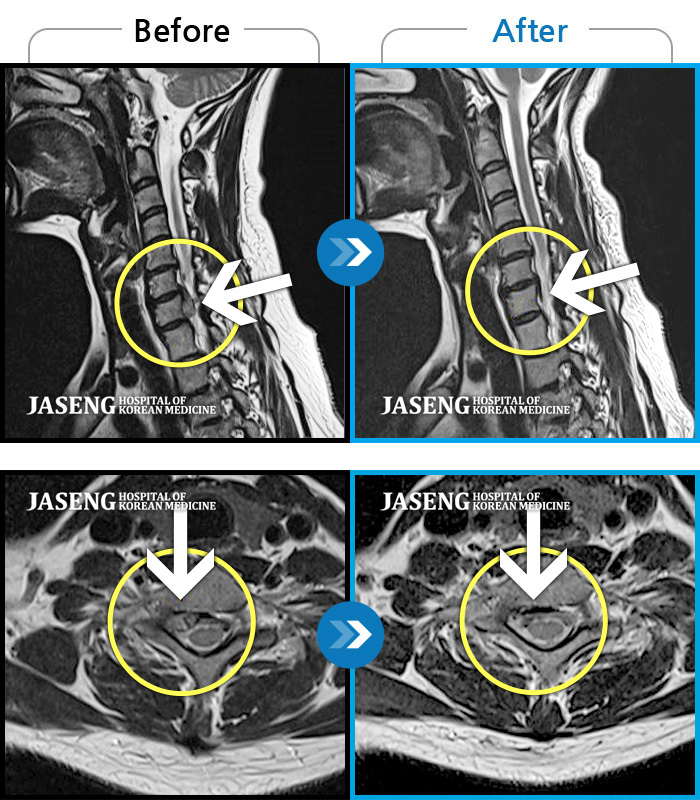

목디스크

도움받은 사례

광주 · 김준수 원장

우측 후경부부터 견갑골내연까지 통증, 우측 팔에서 손가락까지 이어지는 저림감

촬영시기

2023.07.08 ~ 2023.11.07

2023.11.17

조회수 207